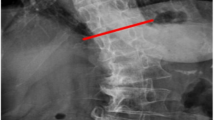

Axial measures were taken from a single slice located at the level of the disc or along/near the lower endplate (lower 1/3rd of the foramen), depending on which provided the fullest and clearest posterior arch anatomy and LMM outlines. All measures were acquired at L4/5 and L5/S1 bilaterally. Patients were excluded if their images showed obvious or apparent surgery from L4-S1, spinal cancer or acute fracture, insufficient image quality, only partial visualization of the LMM at either level, slice overlap artefact through the LMM, distorted or unidentifiable posterior arch anatomy, or did not include the L4/5 or L5/S1 level or T2-weighted axial images.

For this analysis, the muscle cut-off value was defined as the maximum muscle signal intensity peak within the image histogram (Fig. 1a). This method took into account all muscle visible on the image (including psoas, erector spinae, and multifidi muscles) to reduce the errors in measurement values which occur when significant, isolated atrophy of the LMM is present. Once that peak was identified, its value was set as the upper range for muscle signal, with the signal values to the right of the peak encompassing any fat and remaining tissues. Importantly, this peak value was used for determining a reproducible cut-off point of the “purest” muscle for measurement purposes across all imaging cases, not to precisely define pure versus degraded muscle.

While the above noted method was used for most images, occasionally tightly packed double or triple peaks of similar height were present, in which case the peak with the highest signal (i.e., furthest to the right) was used as the cut-off value (Fig. 1b). In approximately 5% of cases, there was very little pure muscle anywhere on the image and thus no obvious muscle peak. In these cases, the muscle cut-off value was visually estimated and cross-checked for appropriateness during the CSA analysis.

Once the peak muscle value was determined, the LMM total CSAs were outlined using protocols developed previously8, with each LMM outlined by following the posterolateral margins of the spinous process and lamina to the facet joint region, descending along the cleavage plane separating the multifidus and longissimus muscles, then medially along the posterior fascial margin to the spinous process (Fig. 2a,b). If any LMM margins were not clear on the selected image, adjacent images from the original imaging series were reviewed to help localize the correct margins. Peak muscle versus remaining tissue CSAs were then determined (Fig. 2a,b), and the proportion (from 0.0 to 1.0) of peak muscle CSA was calculated [peak muscle CSA (cm)/total CSA (cm) = proportion muscle CSA [reported as percentage CSA (% MCSA)]]. The average L4 and L5% MCSA values and the worst % MCSA values for L4 or L5 were determined, with right or left-sided values applied to right or left-sided pathology analysis (i.e., right vs left-sided facet arthrosis or disc herniation apex) and bilateral values used for the remaining central and combined pathology analyses.

Multifidus muscle total CSA and % MCSA. (a) bilateral total CSA (L4), with red and gold highlights indicating the right and left peak muscle CSA, respectively; (b) bilateral total CSA (L5), with blue and pink highlighting the right and left peak muscle CSA, respectively. Note This method did not select all potential muscle signal; only the “purest” muscle tissue was highlighted.